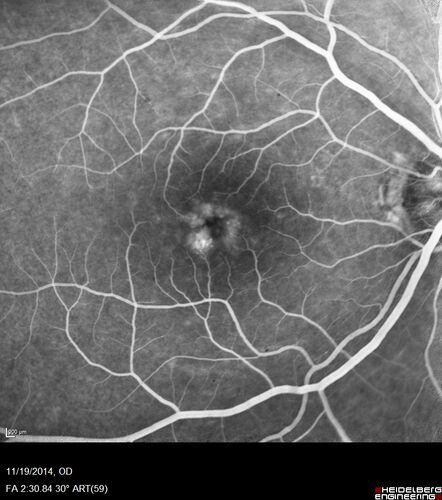

Lamellar Macular Hole - Evoluation over 5 years

65 year old man with Sturge weber and a choroidal hemangioma in the left eye.  (See other images under sturge weber on this website). Has ongoing problem with his left eye.  Now with Blurred vision in the right eye gradually worse the last few weeks.  He has had a vitrectomy in the right eye 4 years ago for floaters.  Laser for tears and cryo in the right eye 5 years ago. He is on Dorzolamide and Lumigan for glaucoma.

VA 20/32 OD, 20/40 OS

IOP 23 OD, 19 OS